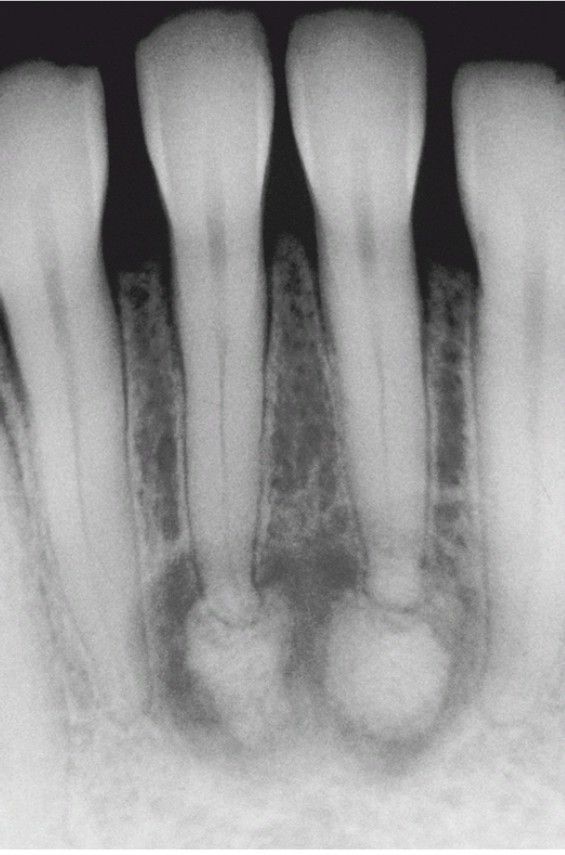

Periapical Cemento-Osseous Dysplasia.

Laterstage lesions exhibiting significant mineralization.